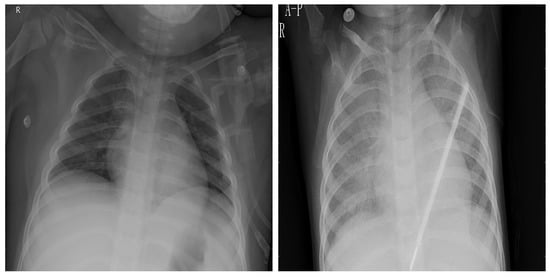

4.5. Explainability